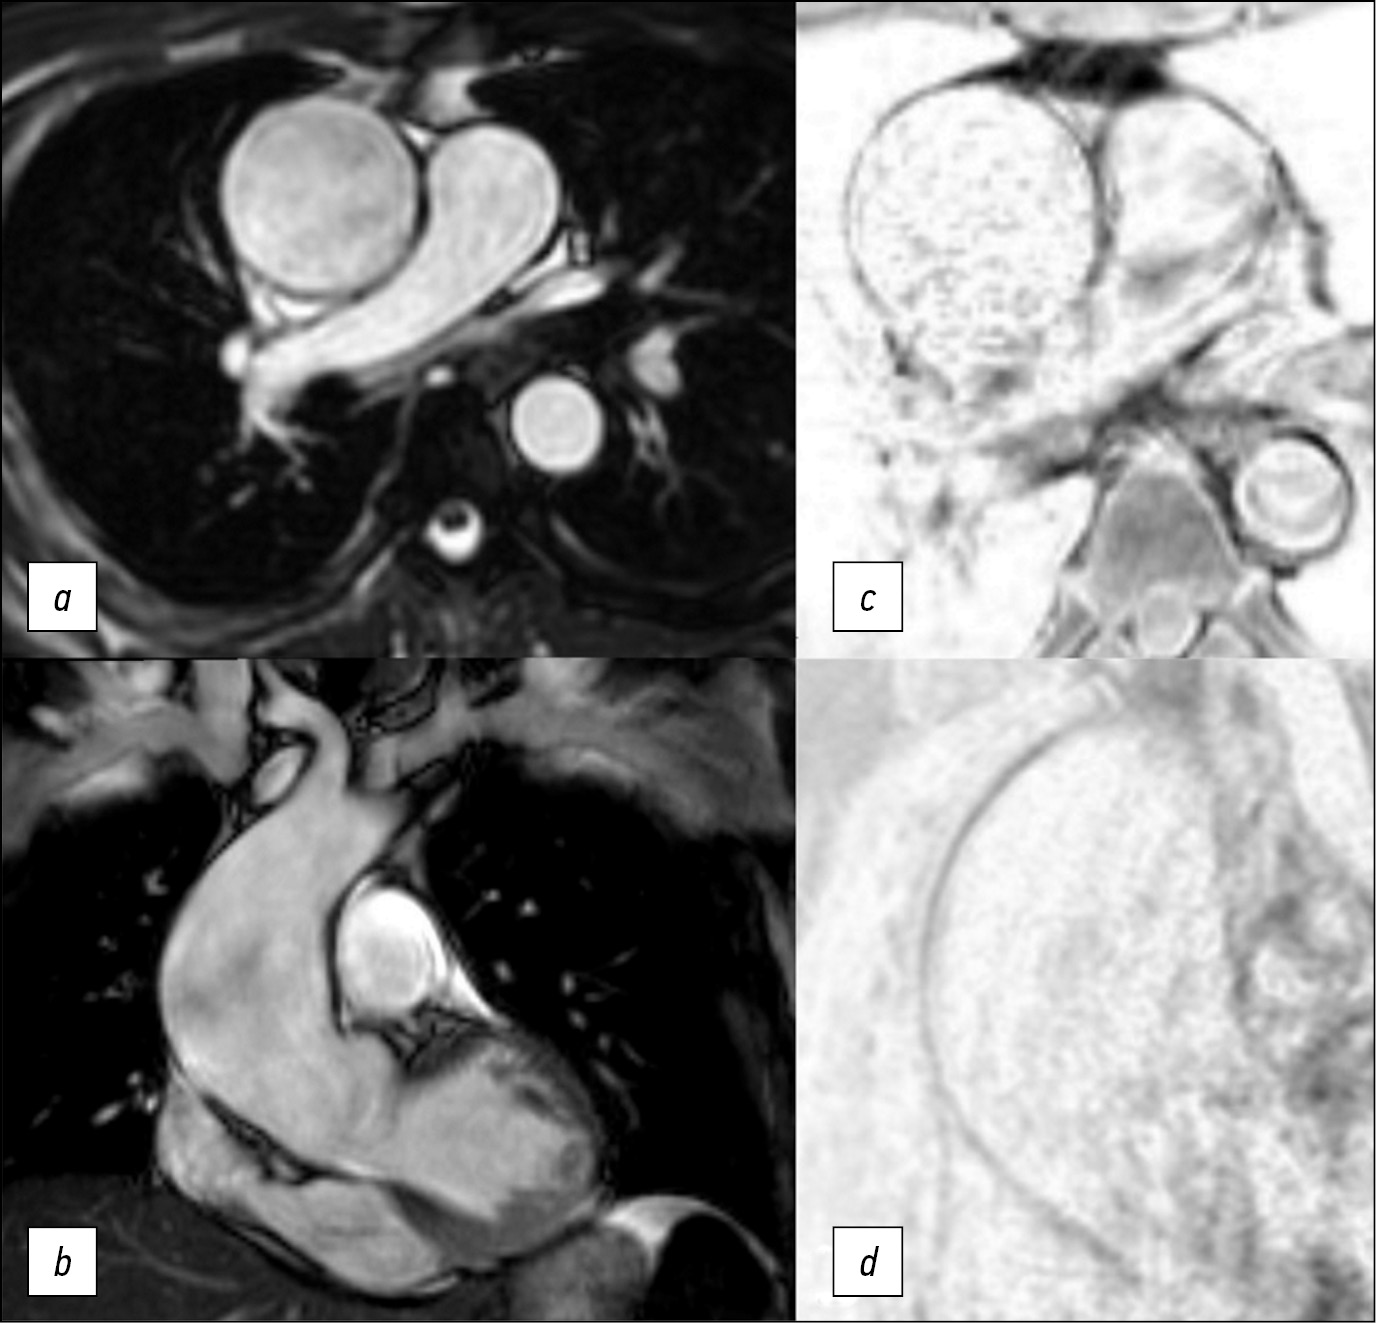

Возможности диагностики: инновационный подход в использовании магнитно-резонансной томографии при аневризме аорты

В статье сообщается об инновационном применении магнитно-резонансной томографии для определения хирургической тактики.

Авторы описывают случай 47-летнего пациента, которому провели исследование методом магнитно-резонансной томографии с последующим хирургическим лечением аневризмы аорты. В отличие от эхокардиографии, этот способ диагностики позволяет увидеть всю грудную аорту, в отличие от компьютерной томографии ― помогает выявить изменения в стенке аорты. С помощью магнитно-резонансной томографии удалось определить дистальный край резекции. Послеоперационный период прошёл без осложнений. По синхронизированным с электрокардиограммой данным проведена оценка структурных изменений стенки аорты и её механические свойства. Важно отметить, что результаты магнитно-резонансной томографии коррелировали с результатами гистологического исследования.

Для эффективного хирургического лечения пациентов с аневризмой аорты необходимо определять степень изменений в стенке сосуда.

Магнитно-резонансная томография стенки аорты ― перспективное направление в диагностике, требующее дальнейшего изучения в многоцентровых исследованиях.